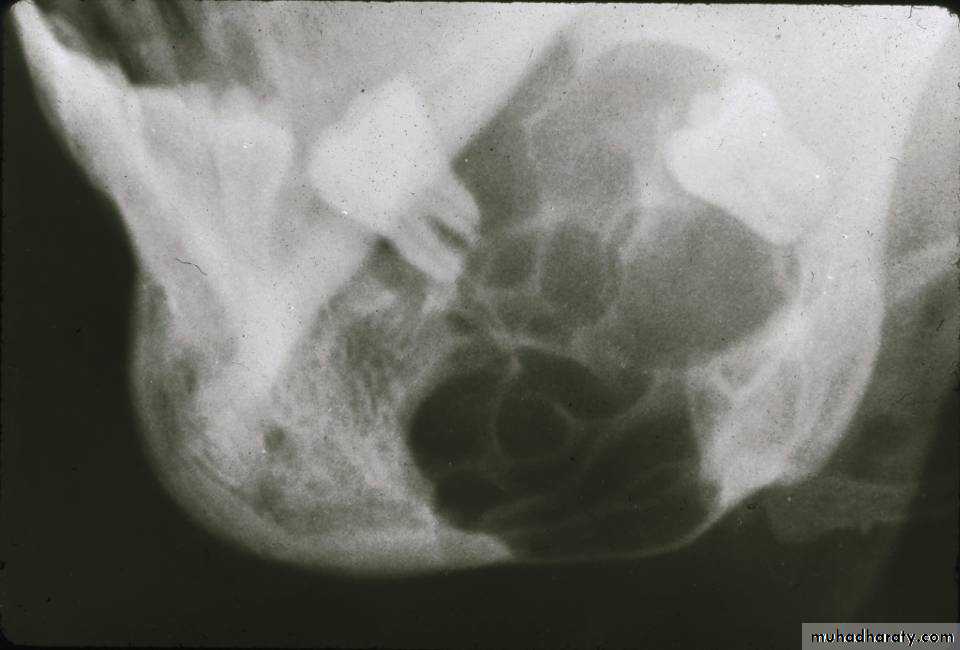

Radiographical appearance• Usually well-circumscribed;

• Multilocular Radiolucency.• (Honeycomb) or (soap- bubble) appearance.

• Recently diagnosed by:

• Computed tomography (CT) scan.

• Magnetic resonance imaging (MRI).